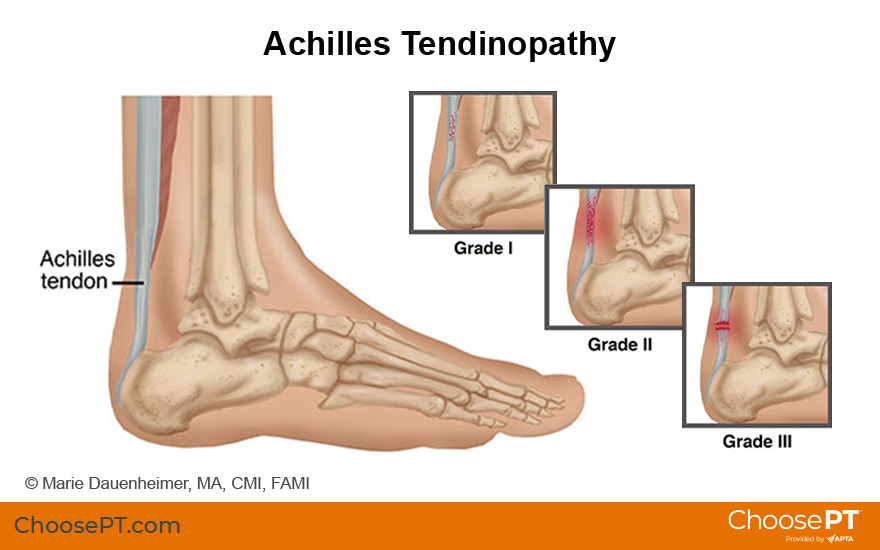

What Is Achilles Tendinopathy?

Achilles tendinopathy is an irritation of the Achilles tendon, a thick band of tissue that runs up the back of the lower leg. This tendon connects the calf muscles to the heel. The term "tendinopathy" refers to any problem with a tendon, either short- or long-term. The Achilles tendon transmits force from the calf muscles to the foot when a person pushes off the ground (such as when running or jumping). It also helps control ankle position when the foot touches back down on the ground.

Achilles tendinopathy occurs when the demand on the Achilles tendon exceeds its ability to function. The condition is most common in people ages 35-55 but can affect anyone. It can occur after a single injury (acute) or with repetitive irritation (chronic). Achilles tendon pain often results from repeated trauma without proper recovery or rest. This can lead to chronic conditions, making it harder to walk, run, and jump. It is most often treated with physical therapy.

Pain can occur along the Achilles tendon or where the tendon meets the heel. The most common area to feel tenderness is just above the heel.